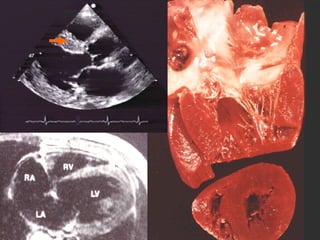

Daño a Órgano Blanco: Corazón:  Hipertensión maligna SNC:  Encefalopatía hipertensiva, Hemorragia cerebral, Infarto cerebral, Isquemia C. Transitoria Riñón:  Nefroesclerosis, Insuficiencia Renal Vasos:  Aneurismas, Disección aórtica

COMPLICACIONES HIPERTENSIVAS: Hipertrofia Ventricular Izquierda Disfunción Diastólica Disfunción Sistólica Insuficiencia Cardiaca Izquierda, Derecha Cardiopatía Isquémica

Daño a ÓrganoBlanco: Corazón: Hipertensión maligna SNC: Encefalopatía hipertensiva, Hemorragia cerebral, Infarto cerebral, Isquemia C. Transitoria Riñón: Nefroesclerosis, Insuficiencia Renal Vasos: Aneurismas, Disección aórtica

COMPLICACIONES HIPERTENSIVAS: HipertrofiaVentricular Izquierda Disfunción Diastólica Disfunción Sistólica Insuficiencia Cardiaca Izquierda, Derecha Cardiopatía Isquémica

CASO CLÍNICO: Femeninade 78 años con edema agudo pulmonar y PA 170/120 mmHg, FC 120 por minuto, S3 apical, estertores crepitantes. ECG: Eje -30o., Voltaje QRS aumentado en derivaciones V5-V6. RX: Cardiomegalia III/IV y HVCP III/IV ECO: Trastorno de relajación y FE 42%

DIAGNÓSTICO: HAS E-2primaria, riesgo C por cifras y daño a órgano blanco (Cardiopatía hipertensiva) Insuficiencia Cardiaca por Disfunción mixta: Sistólica y Diastólica, Clase IV NYHA, Tres Criterios mayores de Framingham